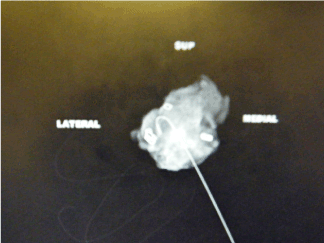

All patients requiring BCS for invasive or pre-invasive breast disease performed by a single oncoplastic breast surgeon within the breast surgery department of the Royal Wolverhampton Hospitals NHS trust between June 2015 and June 2017 were recruited. Each excised breast lesion was orientated by sutures and titanium clips to identify the superior, medial and lateral aspects as shown in figure 1.

Figure 1. Breast Specimen orientated with sutures.